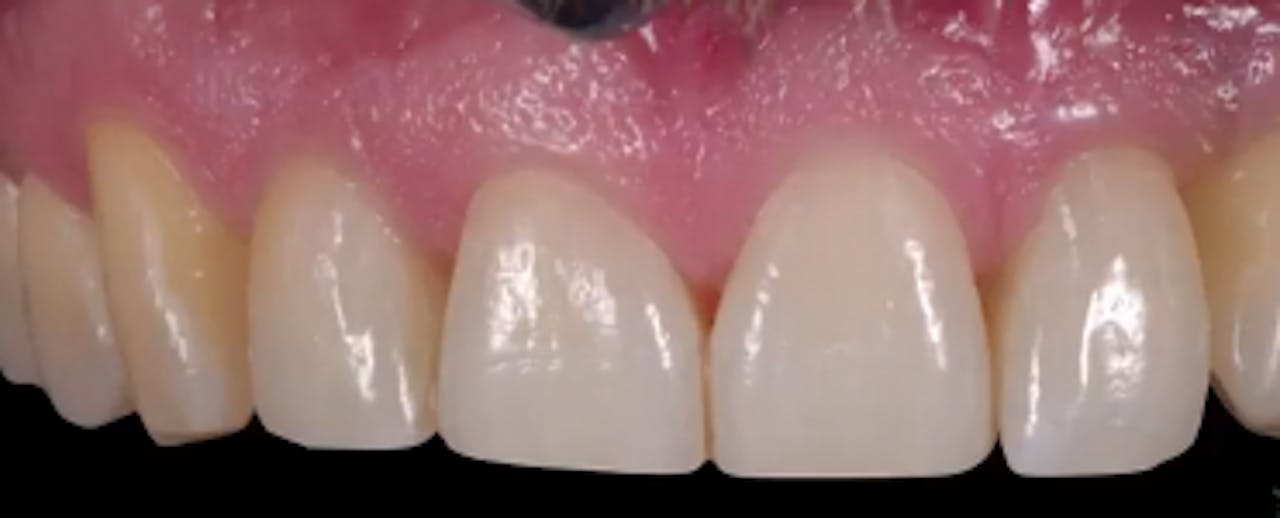

CLINICAL VIDEO Anterior Implant Placement with Immediate Temporization Gide Dental Reviews Premiere provider of online dental education. Gide dental institute, los angeles, california. Find reviews, ratings, directions, business hours, and book appointments online. 31,762 likes · 74 talking about this · 887 were. Gide dental | 280 followers on linkedin. Read 26 customer reviews of gide dental center, one of the best. Dive deep (at your own pace) in a comprehensive. Gide Dental Reviews.

CLINICAL VIDEO Anterior Implant Placement with Immediate Temporization Gide Dental Reviews Clinical videos, expert interviews, live broadcasts over. Premiere provider of online dental education. Evidence based video education at its best. Dive deep (at your own pace) in a comprehensive online master class or residency with topics covering implant dentistry, esthetic dentistry,. Read 26 customer reviews of gide dental center, one of the best. Gide dental | 280 followers on linkedin.. Gide Dental Reviews.